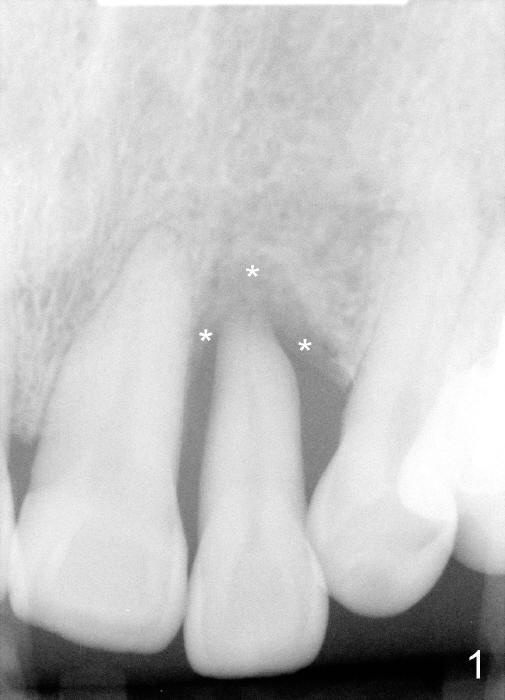

1. Place implant as lingual and apical as possible, cosmetic

3. Gingival retraction cord #2, can be overlapped, stop bleeding, push gingiva away from prep, and most important prevent Titanium shaving from being trapped in socket

4. Rinse off metal shaving with normal saline or other before cord removal, bone graft or cementation of the provisional